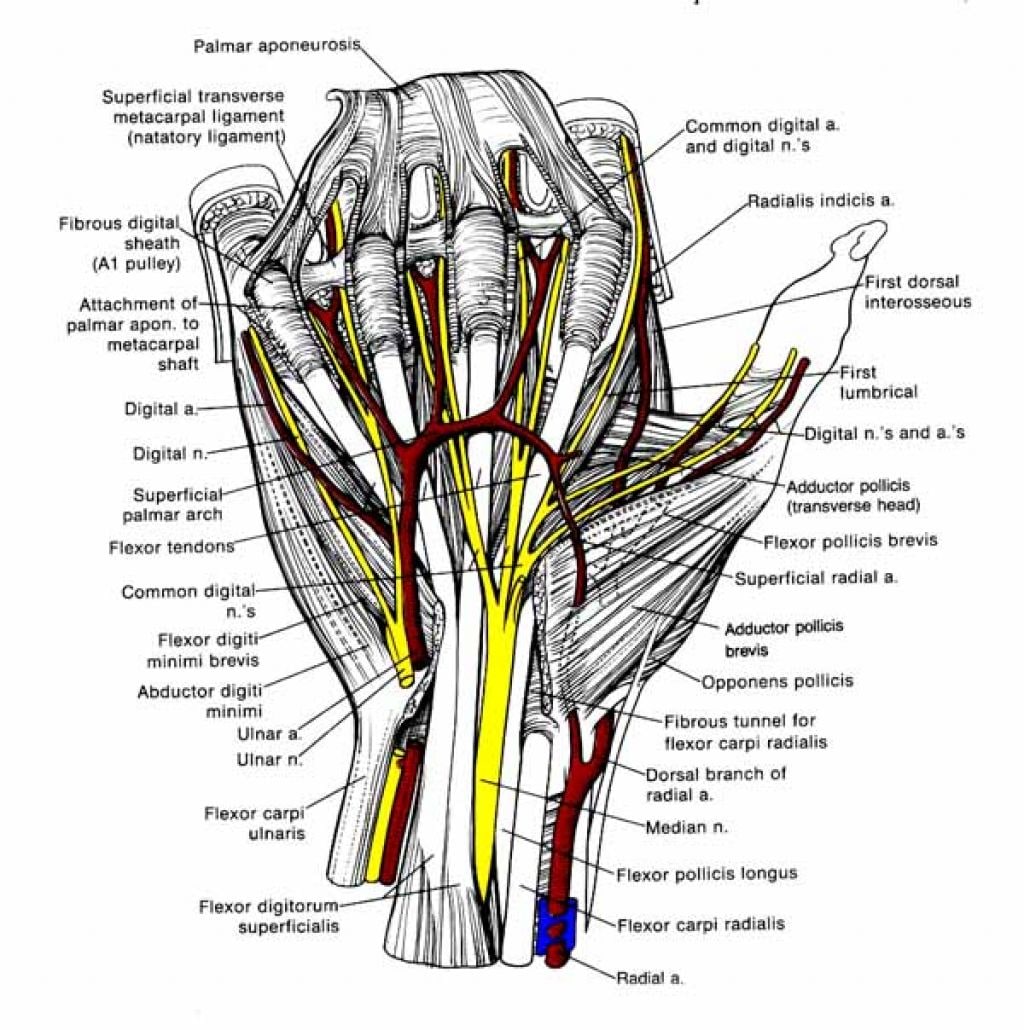

Анатомия кисти руки и строение костей